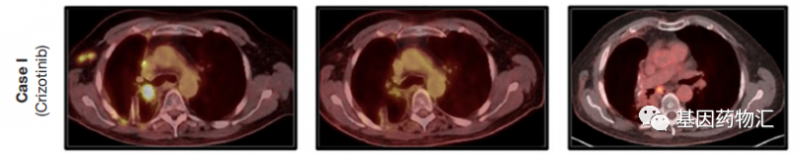

患者72岁,早年曾经吸烟,确诊时属于局部晚期肺腺癌,原发病灶活检提示存在ROS1基因重排。患者接受了根治性同步放化疗,病情得到控制。

此时患者的分期已经处于转移期,二代测序提示了SLC34A2-ROS1融合、CDKN2A缺失和TET2 P1617fs86突变,颅脑成像提示不存在脑转移。因此,患者开始接受克唑替尼一线治疗,250 mg每天两次。

从疗效上来说,仅2个月的用药之后,患者的肿瘤负荷就开始非常显著地降低,但患者经历的不良事件比较多,包括疲劳、胃肠道紊乱(交替腹泻和便秘)、下肢水肿、食欲下降、睾酮水平降低等等,经过评估,医生为他调整了方案,降低克唑替尼的用药剂量至250 mg每天一次。

患者的缓解持续了整整24个月。至于后期的治疗,医生表示,在患者影像学提示进展之后,会根据活检结果以及影像学结果仔细评估,考虑跨适应症进行劳拉替尼治疗,或者免疫检查点抑制剂+化疗,或者克唑替尼治疗联合局部治疗(如放疗)。